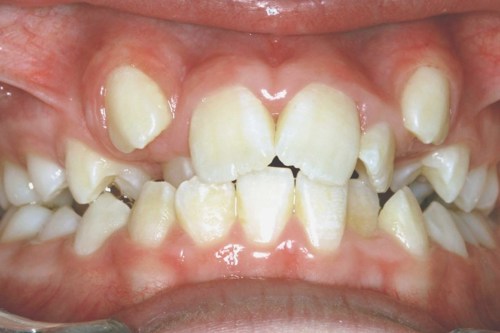

Nedenfor ser du et eksempel på en behandling, der kun har varet 16 måneder. Efter selve tandretningen, skal man regne med at gå med en holdebøjle i flere år, så tænderne ikke rykker tilbage på deres gamle skæve plads.

Billederne viser et tandsæt før tandretning og tandsættet efter 16 måneder med fast bøjle.